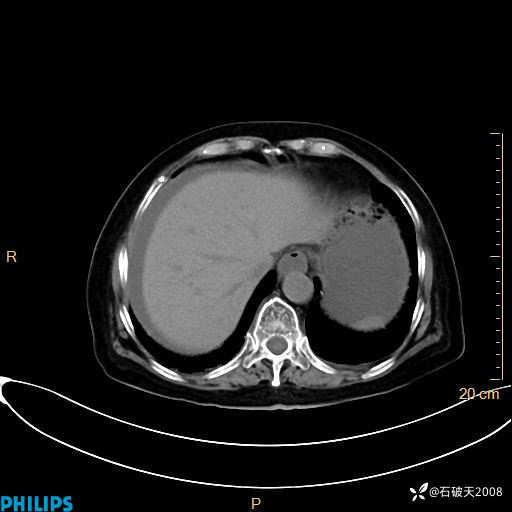

动脉期